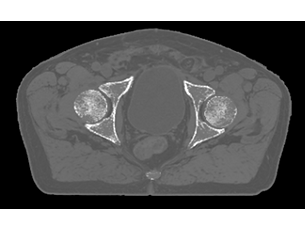

Versatile arrangements of diagnostic quality dStream coils allow you to achieve outstanding image quality with the patient in treatment position. You can perform pelvis, abdomen, brain, head/neck, and spine scans tailored for radiotherapy planning – with intuitive patient setup and minimal coil handling. - A one table solution

Our innovative MRCAT (MR for Calculating ATtenuation) clinical applications lets you plan radiation therapy using MRI as primary imaging modality. Within just one, fast MR exam, MRCAT provides both excellent soft-tissue contrast for target and OAR delineation and CT-like density information for dose calculations. This not only extends the benefits of MRI’s excellent soft-tissue contrast to radiotherapy planning, but it also eliminates arduous, error-prone CT-MRI registration from the process, reducing uncertainties and complexity.

As a plug-in clinical application to Ingenia MR-RT, MRCAT Prostate + Auto-Contouring provides attenuation maps and automated, MR-based contours of prostate and organs at risk in as little as 20 minutes – all in a repeatable ‘one-click’ workflow.

MRCAT Pelvis lets you plan radiation therapy using MRI as a single modality solution. Within just one MR exam, MRCAT Pelvis provides excellent soft-tissue contrast for target and OAR delineation, and continuous Hounsfield units for dose calculations. MRCAT (MR for Calculating ATtenuation) data can be used for export to treatment planning systems for CT-equivalent** dose calculations. In addition, MR-based imaging enables CBCT-based positioning based on soft-tissue contrast with the look and feel of CT.